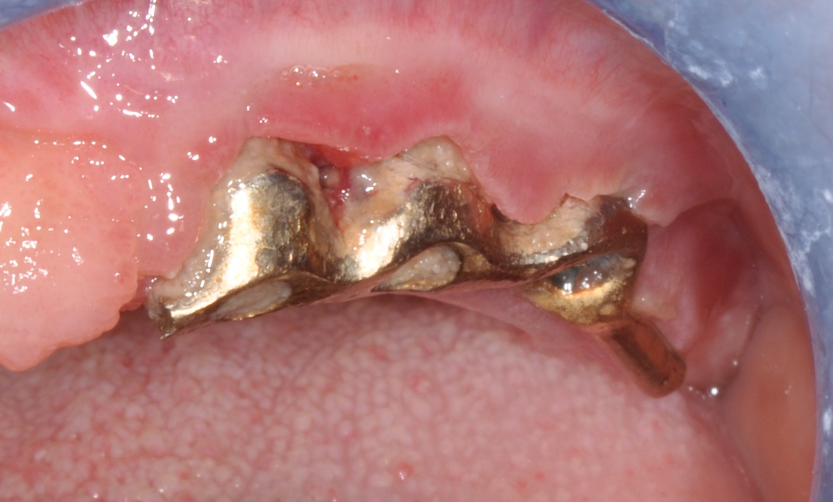

Second step of prevention can be carried out during the surgical phase: a correct positioning of the fixture can help the technician in constructing a correct prosthesis and, consequently, the periodontologist in checking the implant health, the hygienist in cleaning effectively the peri-implant area13 and the patient in keeping an high standard home-care. An ineffective care leads to the development of inflammatory reactions that can be kept hidden under the the prostheses and be unrevealed until their removal. (Fig.4) Particular attention should be given to reach an appropriate amount of keratinized peri-implant tissue: its presence can be beneficial for the maintenance of an adeguate oral hygiene.13 Long abutments and implant placement at sub-mucosal level cannot be considered a good choice from the periodontal point of view since they may create a deep probing depth since the very beginning of the implant-born restorations’ life.13

Fig.4: Case 1. Clinical appearance after the prosthetic crown removal.